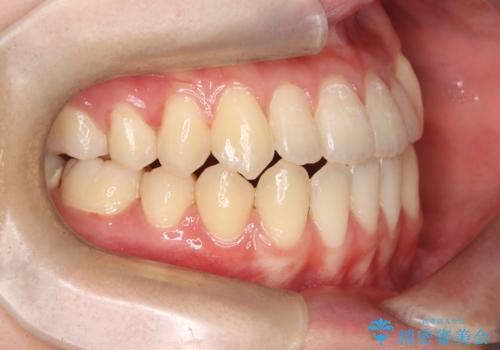

診査の結果、すでに下顎前歯の抜歯が行われていましたが、マウスピースの適合が著しく悪くなっており、歯が計画通りに動いていない状態でした。また、歯を支える骨の厚みや歯肉の薄さを考慮すると、このままマウスピースによる傾斜移動を続けるのは歯肉退縮(歯茎が下がること)のリスクが非常に高いと判断。

装置の変更と歯肉への配慮: ワイヤー矯正は歯の根(歯根)を平行に移動させる「歯体移動」を得意としています。本症例では、歯肉退縮を防ぐために、歯の傾きを精密にコントロールしながら抜歯スペースを閉じる必要がありました。ワイヤー装置を用いることで、インビザラインでは難しくなっていた三次元的な細かい調整を可能にしました。

リカバリーのプロセス: 適合が悪くなったインビザラインを一旦中止し、ブラケットを装着。停滞していた歯の移動を再開させ、上下の正中(中心)や奥歯の咬み合わせを一つひとつ整えていきました。